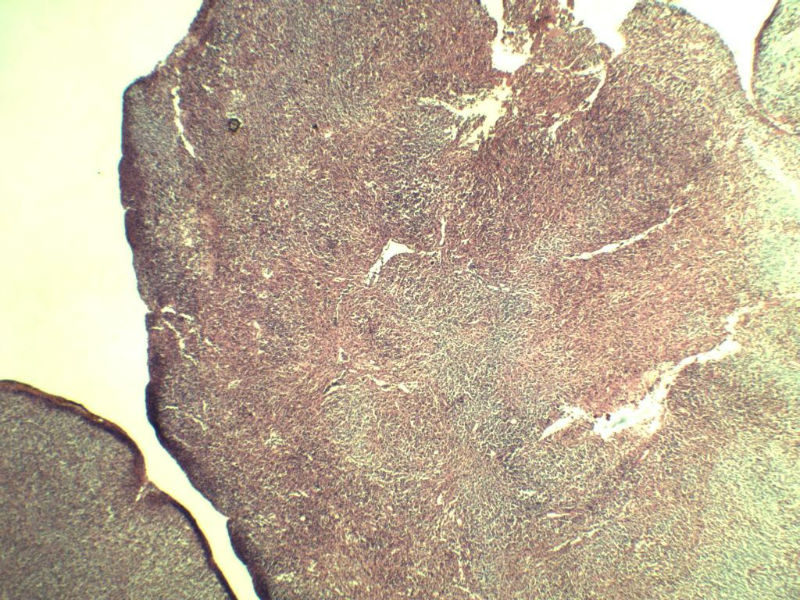

男,38岁,腹股沟 多枚淋巴结活检  直径 0.2-0.5 请各位老师看看 是什么 谢谢了!

"畏寒,发热咳嗽1年,加重伴腹部疼痛2月" 2月前患者感腹部疼痛不适伴大便呈稀大便,量不详,伴腰骶部疼痛,胸片:纵膈及右肺门多发性淋巴结肿大,进一步完善胸部CT:右肺及中叶病变,纵膈及肺门多发淋巴结肿大,结核性可能,脾脏增大,PPD(-),1个月来患者出现中上腹食欲不振,体重进行性消瘦,全身疲乏无力,3天前到医学院就诊,腹部B超:右肝囊肿,胆囊壁毛糙,脾大,胰周多个减弱回声,淋巴结不能除外,腹水,血常规示:WBC16.36x109 /L,N%14.25%,RBC2.63x1012/L ,HGB 66g/L 。右侧腋窝及腹股沟可扪及多枚淋巴结,压痛,无明显粘连。

名称:图2

副皮质区增生,纤维化显著,细胞呈多形性,有一些多核巨细胞及一些异型细胞,病理性核分裂易见,胞浆红染,散在的小淋巴细胞,T细胞淋巴瘤不能除外,树突细胞肉瘤等鉴别。免疫标记。CD21、CD3、CD5、CD10、CD20、CD79a、PD1、CD68、CXCL13、KI-67、CD68、CD163等,据切片选择。不知对否。

淋巴结正常结构破坏,可见大的异型细胞,上皮样或梭形,恶性肿瘤,依据病史,首先考虑淋巴造血系统疾病,大中小细胞混杂,大细胞多,形态多样,可见多核瘤细胞,除以上考虑外需鉴别间变大、组织细胞肉瘤、指状突/树突细胞肿瘤、HL等,还需排除肉瘤或癌转移,尽管病人年轻,加上ALK、CK、S-100、CD1a。